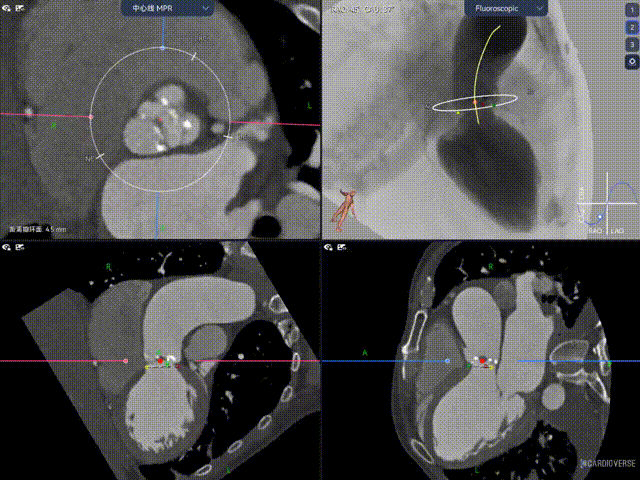

术前CT评估

Type1型二叶瓣(L-R),中度钙化,钙化集中在左右融合脊与无冠窦瓣叶两侧、LN交界处,Annulus直径23.3mm,LVOT25mm,向下敞口结构,限制区集中在瓣上6-9mm处,最窄空间预估19.8mm。窦部空间正常、LR融合,无冠脉风险;主动脉瓣环水平夹角59.6°,横位心,左室腔扩大,有一定循环崩溃风险。外周双侧入路良好、内径可、无钙化、双侧入路能够支持18F大鞘通过,右股中分叉,主动脉弓距短,锐角弓。